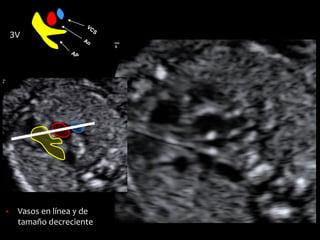

▪ Vasos en línea y de

tamaño decreciente